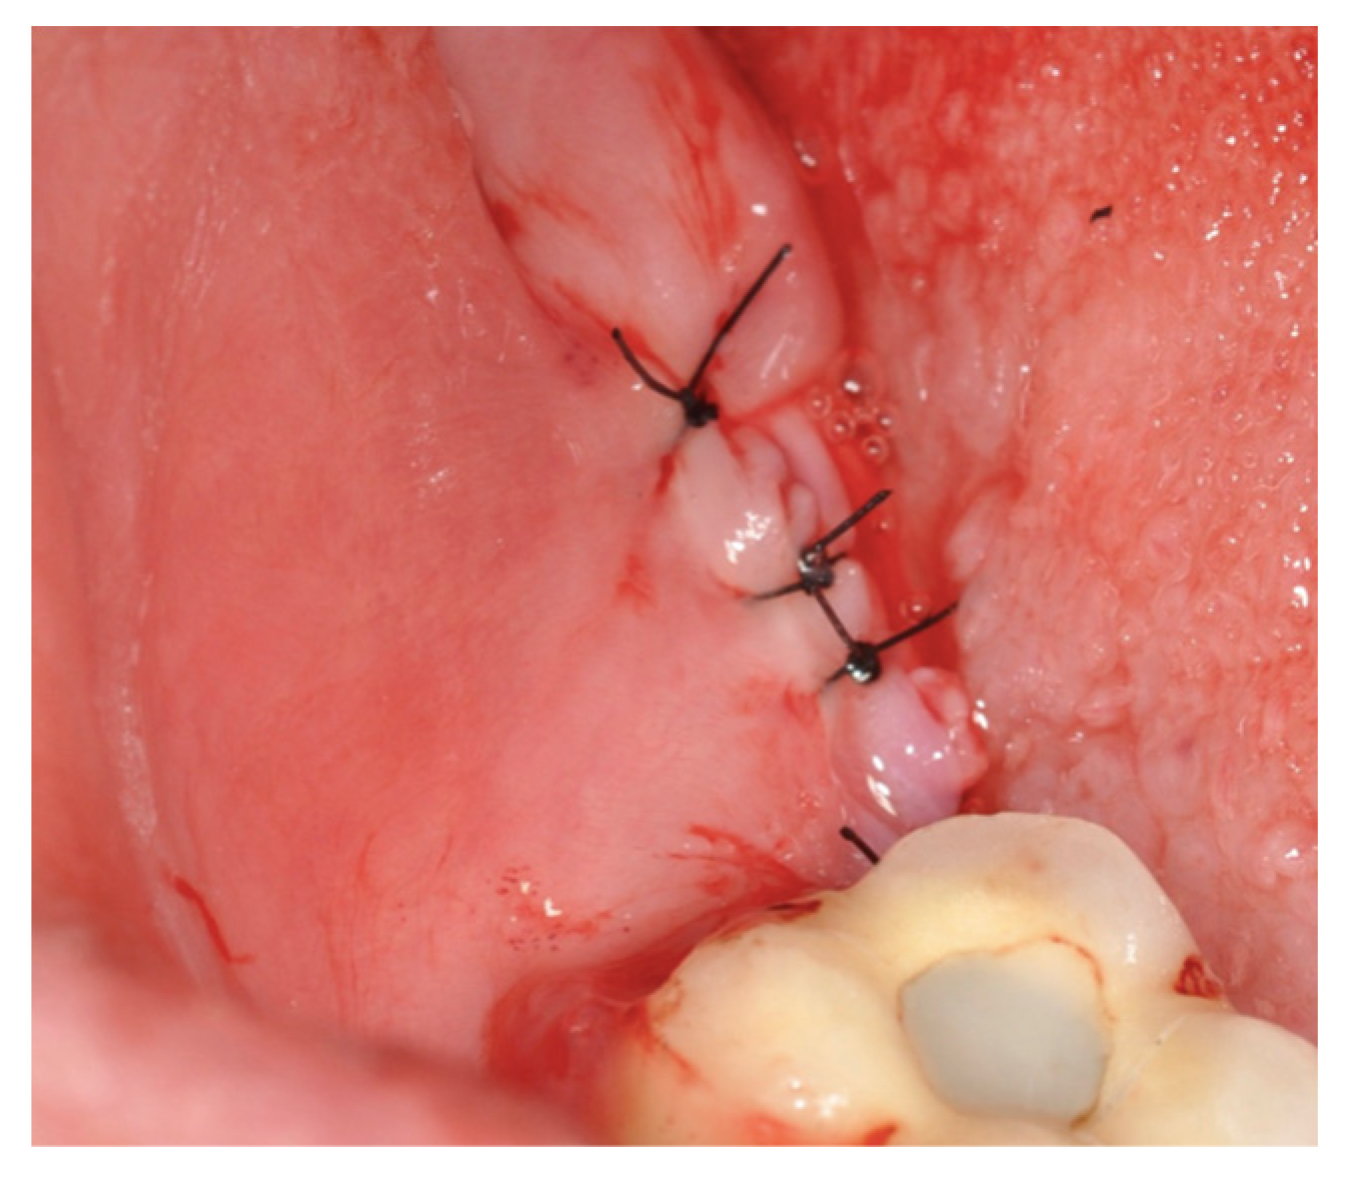

2.2. Surgical Technique

3. Results